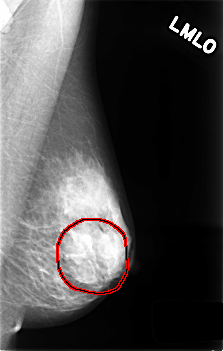

C_0430_1.LEFT_MLO

FILE: C_0430_1.LEFT_MLO.OVERLAY

TOTAL_ABNORMALITIES 1

ABNORMALITY 1

LESION_TYPE MASS SHAPE OVAL MARGINS OBSCURED

ASSESSMENT 3

SUBTLETY 4

PATHOLOGY BENIGN_WITHOUT_CALLBACK

TOTAL_OUTLINES 1